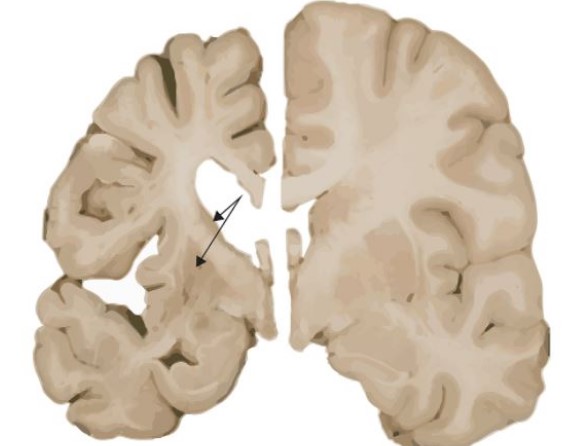

헌팅턴병은 중추신경계에 영향을 미치는 유전적 퇴행성 질환입니다. 이 병은 주로 중년기에 증상이 시작되며 신체 운동, 인지 능력, 정서에 광범위하고 심각한 영향을 미칩니다.

헌팅턴병은 HTT 유전자의 변이로 인해 발생하는데 이 유전자 변이는 염색체 4의 단완에 위치하며, 특히 CAG(시토신-아데닌-구아닌) 염기서열이 정상적인 범위를 넘어서 반복되면서 발생합니다.

정상적인 사람에서는 CAG 반복이 10-35회 사이지만, 헌팅턴병 환자에서는 36회 이상, 때로는 수백 회에 이르기도 합니다.

이러한 과도한 반복은 비정상적인 헌팅틴 단백질을 생성하며, 이 단백질은 뇌의 특정 신경세포에 손상을 입혀 점차적으로 죽음을 초래합니다.